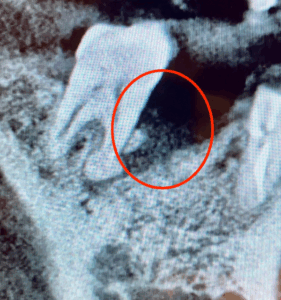

抜歯後、時間をおいてインプラントを埋入しました。抜歯時に骨の吸収が激しいところがあったため、インプラント埋入時に骨造成(自分の骨や人工骨などを使って骨を増やし、骨の土台を作る外科的な処置)も一緒に行いました。

画像がこちらになります。

2枚目の写真はインプラントを埋入して4ヶ月ほどたった時の画像です。インプラント脇の再生治療を行なった場所は、しっかり骨ができているのがわかります。